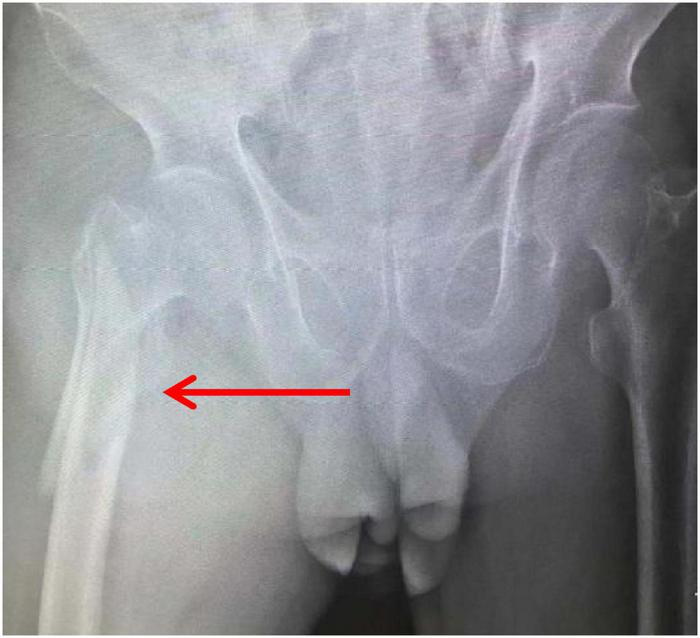

An 81-year-old male patient was hospitalized for right hip pain and restricted movement resulting from a fall that occurred 8 h ago. The X-ray revealed fractures in the right femoral trochanter and proximal femur. The patient has a history of high blood pressure. He received low-molecular-weight heparin treatment while in the hospital. The D-dimer level measured 13.79 mg/L. On the second day of admission, the patient underwent a bedside X-ray and turned over, causing a drop in finger pulse oxygen levels from 98% to 94%. The heart rate was 89 bpm, and the blood pressure was 161/74 mmHg. The patient did not experience any discomfort. An immediate deep vein ultrasound examination of both lower extremities revealed thrombosis in the right superficial femoral vein, popliteal vein, posterior tibial vein, and intermuscular vein of both calves. CTPA revealed the presence of blood clots in both lungs. After being moved to the pulmonary department for standardized anticoagulant treatment, the patient experienced notable improvement. Figures 1–3 display the imaging data.

FIGURE 1

CTPA image of the patient before treatment (arrow indicates the site of embolism).

X-ray.